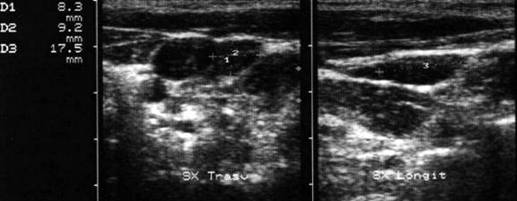

Lob stg. in proiectie longitudinala si trasversala.

Femeiede 49 ani.

Mic nodul calcificat in lobul stang al tiroidei.

Este vizibil o imagine circulara hiperecogena, cu con de umbra posterioara.

Lob stang in proiectie longitudinala si trasversala.

Femeie de 61 ani. Mic nodul

calcificat localizat paraistmic anterior in lobul stang, de 7x8mm.

Este evident conul

de umbra posterioara.